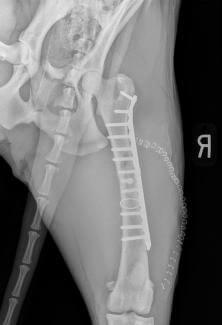

Femur